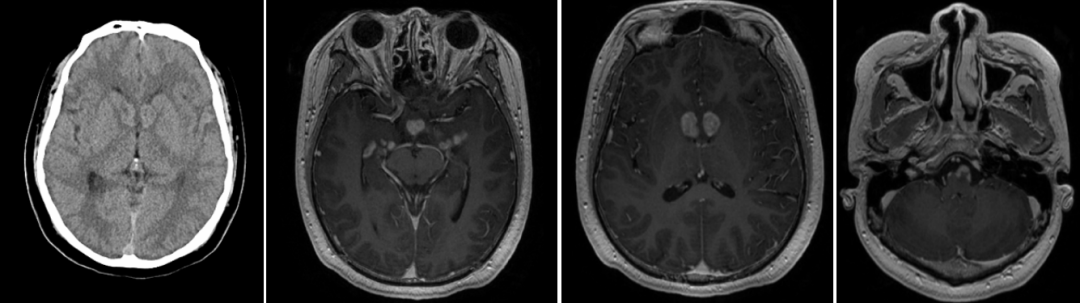

复查增强头颅MRI,提示两侧脑室旁、鞍上池区、松果体区、左侧额叶、右侧枕叶、两侧颞叶、桥脑、两侧小脑半球、延髓左腹侧,见多发大小不等结节状、团片状异常信号,增强后呈结节样、串珠样明显强化影(图1)。